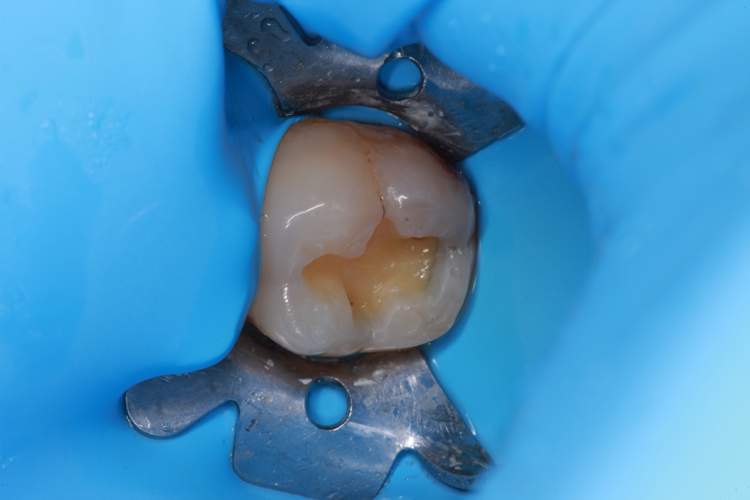

Technically, the procedure was very efficient. After the placement of rubber dam, the amalgam restorations (Fig. 1) and any signs of caries were removed (Fig. 2).

Fig. 1: Failed amalgam restoration. Fig. 2: Amalgam and decay are removed and tooth is prepared with ACTIVA BioACTIVE-RESTORATIVE.